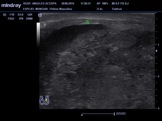

TUMOR VESICALTumor en piso vesical por USG